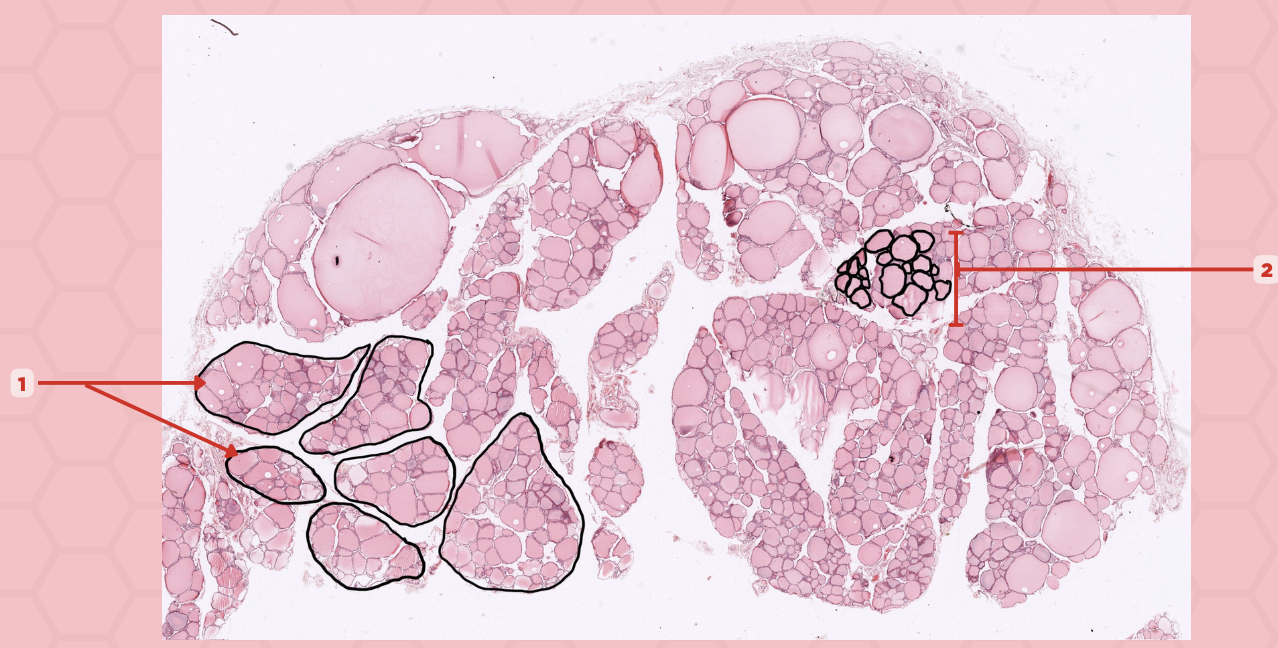

Pancreas

Identify the specimen.

Islets of Langerhans

Identify the structure labeled as 1.

Pancreatic Acini

Identify the structure labeled as 2.

Reticular Tissue

Identify the structure labeled as 3.

Beta-cells

Which cells occupy the central area of #1?

Pancreatic Acini

#3 delineates the pale- staining cells from the darker-staining cells. What do you call the darker-staining cells?